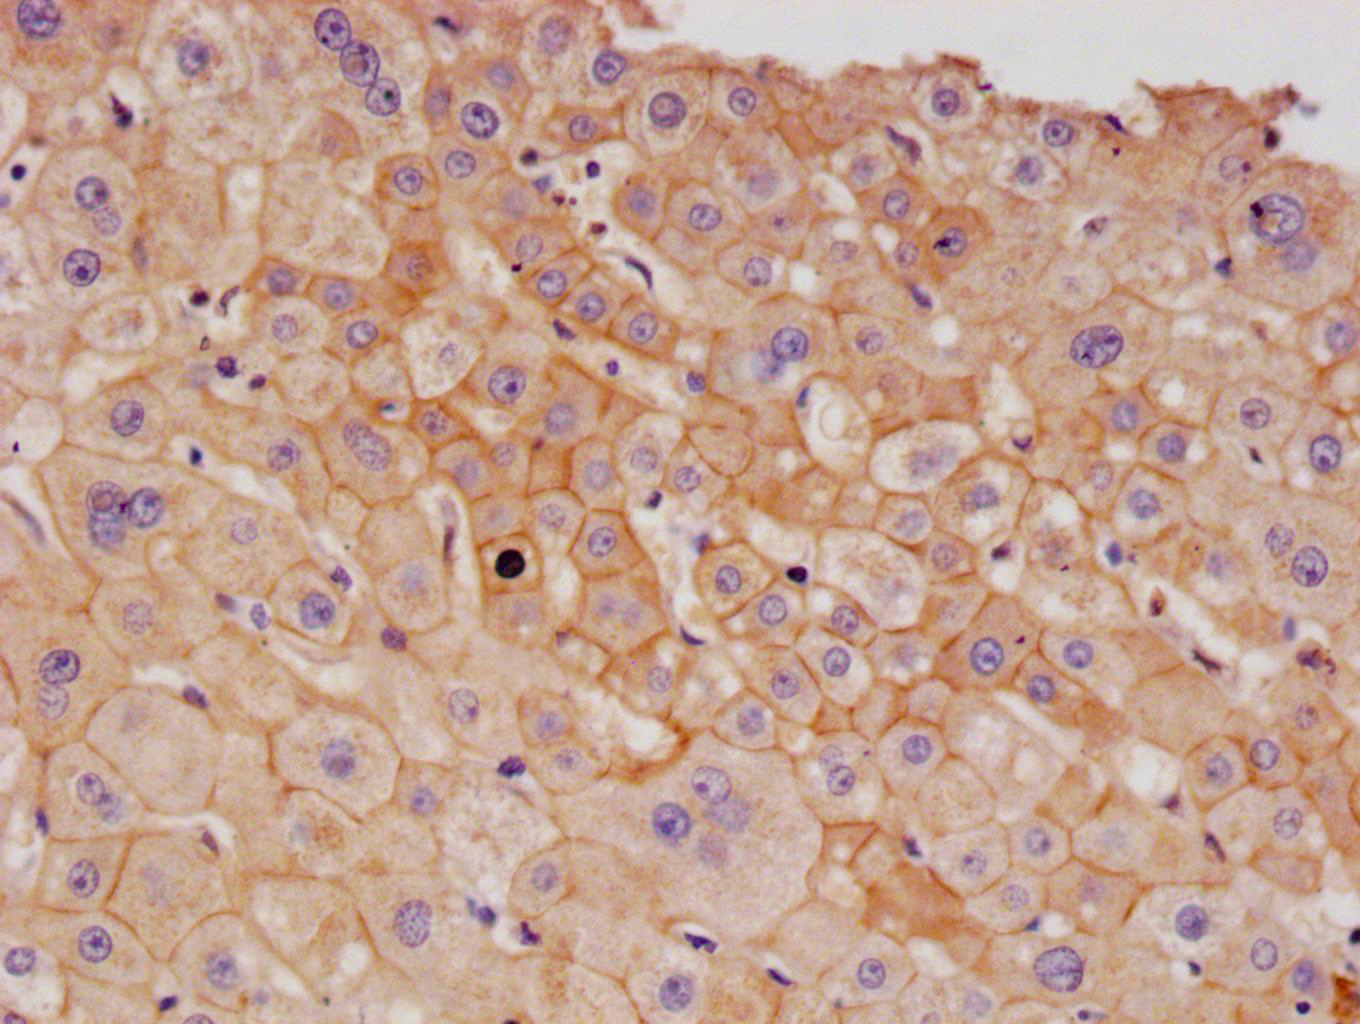

IHC image of CSB-RA437652A0HU diluted at 1:100 and staining in paraffin-embedded human liver cancer performed on a Leica BondTM system. After dewaxing and hydration, antigen retrieval was mediated by high pressure in a citrate buffer (pH 6.0). Section was blocked with 10% normal goat serum 30min at RT. Then primary antibody (1% BSA) was incubated at 4°C overnight. The primary is detected by a Goat anti-rabbit polymer IgG labeled by HRP and visualized using 0.05% DAB.